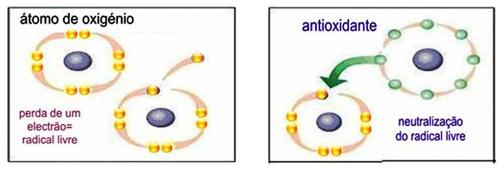

Os antioxidantes são um conjunto heterogéneo de substâncias formadas por vitaminas, minerais, pigmentos naturais e outros compostos vegetais e, ainda, enzimas que bloqueiam o efeito prejudicial dos radicais livres.

Os radicais livres são constantemente produzidos durante o funcionamento normal da célula, na maior parte sob a forma de espécies reativas de oxigénio (ROS). Os radicais livres são átomos quimicamente ativos ou moléculas que apresentam um número ímpar de eletrões na sua órbita externa (Figura 1). Como apresentam um ou mais eletrões ímpares, os radicais livres são altamente instáveis, prejudicando as células, podendo oxidar e danificar lípidos celulares, proteínas e ADN, inibindo a sua função normal e conduzindo a várias doenças. Quando a produção de radicais livres é superior à capacidade dos antioxidantes, ocorre o denominado processo de stresse oxidativo.

A manutenção do equilíbrio entre a produção de radicais livres e as defesas antioxidantes é uma condição essencial para o funcionamento normal do organismo. Alguns nutrientes (vitamina C, E e A e minerais) e produtos naturais (carotenoides, flavonoides, e outros polifenois), Zinco, Selénio e Licopeno são antioxidantes, estas substâncias impedem a oxidação de moléculas que constituem as membranas das células e outros elementos importantes para o metabolismo celular (Figura 1). Assim, os antioxidantes são de extrema importância, uma vez que, ajudam na prevenção do desenvolvimento de várias doenças como o cancro, doenças cardíacas, doença de Alzheimer, artrite reumatoide entre outras.

Figura 1 – Formação de radicais livres e sua neutralização pelos antioxidantes.